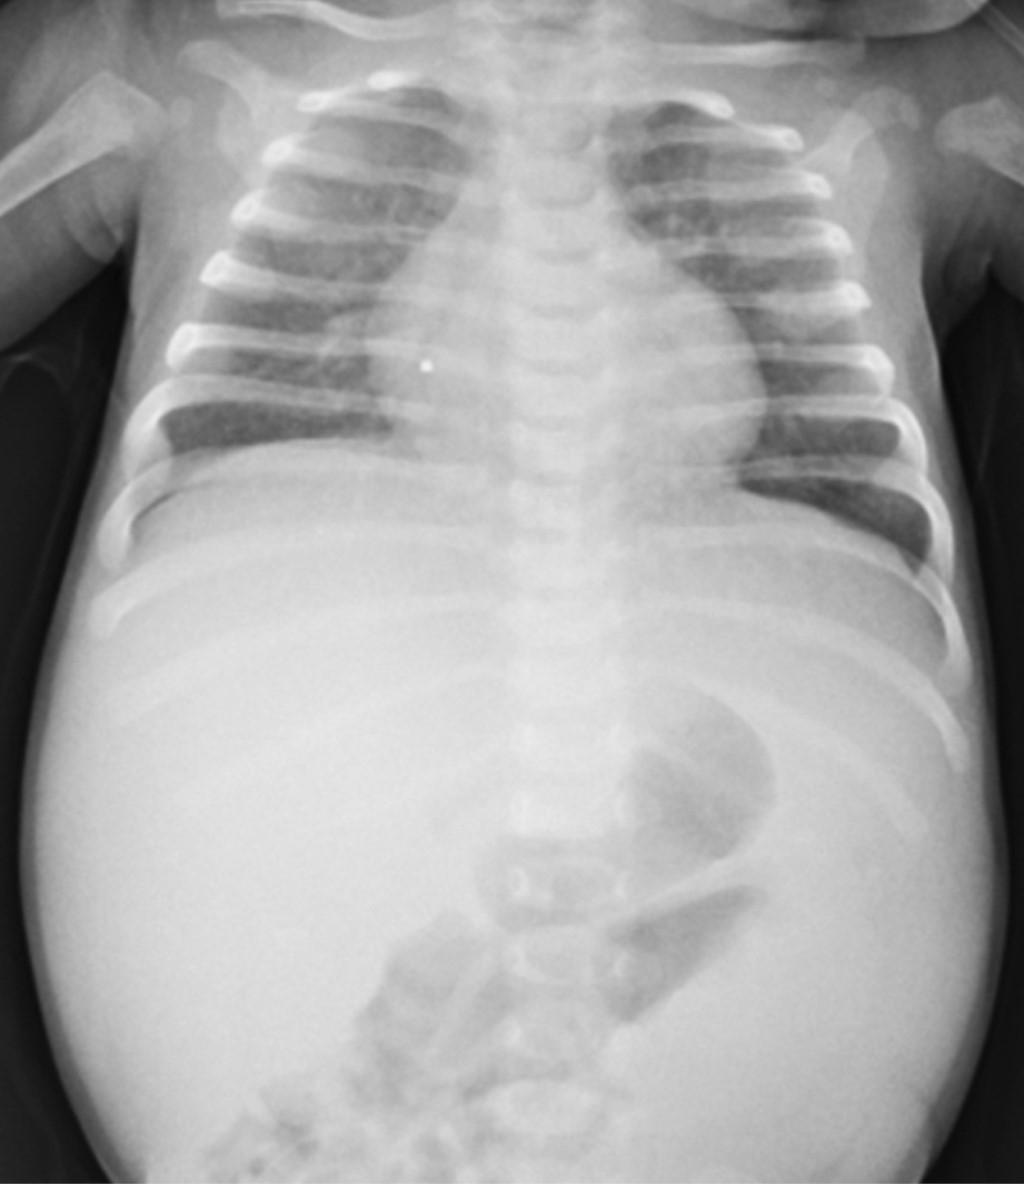

Femenino de dos meses de edad previamente sana. Acude a nuestro hospital por un mes de evolución con distensión abdominal, palidez y petequias en extremidades. A su valoración estaba irritable, pálida, con petequias generalizadas, dificultad respiratoria moderada, hepatoesplenomegalia, taquicardia y SatO2 ambiental en 89%. Sus exámenes reportaron bicitopenia e hiperleucocitosis, sin hallazgos de síndrome de lisis tumoral (Tabla 1). La radiografía de tórax (Figura 1) tenía infiltrados bilaterales. El aspirado de médula ósea reportó blastos 95.5% tipo morfológico L1 (Figura 2) y el inmunofenotipo leucemia linfoblástica aguda Pro-B con translocación cromosomal 12;21.

Figura 1